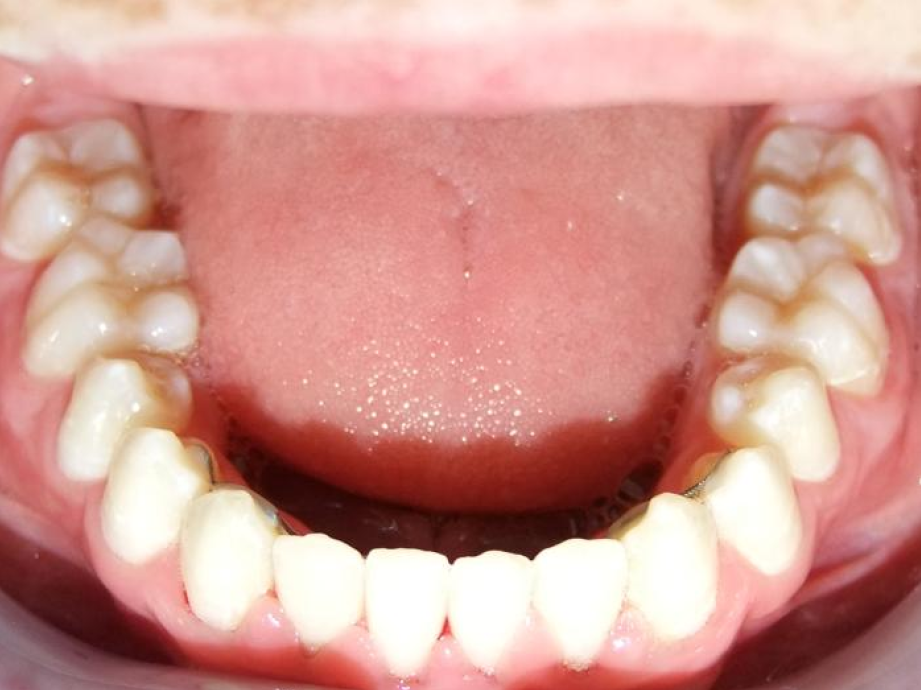

eindfoto

Leeftijd bij aanvang: 9 jaar

1-6 Bonded Hyrax + partieel vast onderkaak + TransForce onderkaak

7-13 Twinblock

13-22 volledig vast onder- en bovenkaak + rotator

Retentie: wrap en c-c bar

Leeftijd bij retentie: 12 jaar